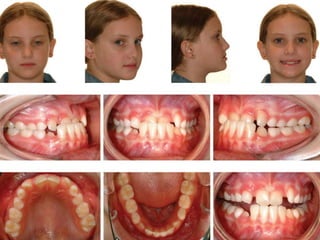

A 7 year-old boy was initially referred by his GDP

for the removal of two supernumerary teeth

present in the upper midline. He presented in

the early mixed dentition. The supernumerary

teeth were removed and the patient reviewed 1

year later when he presented with a very

irregular and rotated upper incisors .A course of

264 appliance therapy was prescribed.

Initially, all four incisors were bonded with

bands place on both upper first

permanent molars and an initial aligning

wire of 0.012 inch nickel titanium due to

the severe rotations associated with the

upper incisors. Progression was via a

0.016 inch nickel titanium achwire to a

0.018 × 0.025 inch nickel titanium

archwire with a working archwire of

0.019 × 0.025 inch stainless steel.

Powerchain was used for a single visit to

close any remaining anterior spacing.

Once a positive overjet and overbite were

established the appliance was removed,

and a palatally-bonded retainer

cemented. Total active orthodontic

treatment time was thirteen months.

Intra-oral photographs after alignment

of incisors

Post-treatment photographs.

Palatal bonded retainer